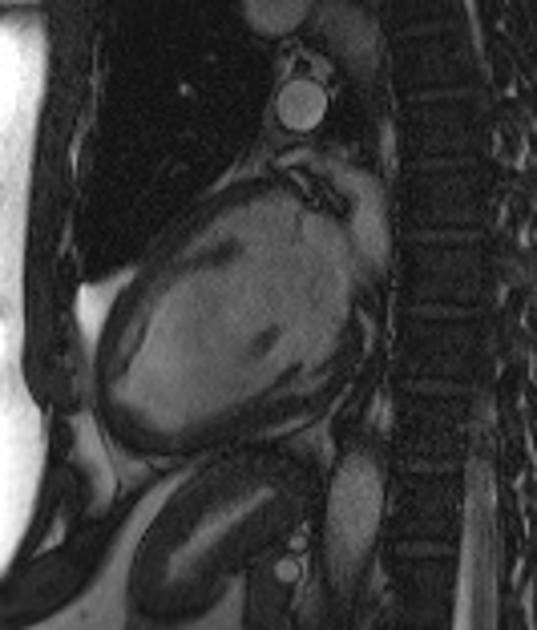

Early gadolinium phase

MRI•Early gadolinium phase•1 / 3

- Đối với hình ảnh gadolinium thì sớm (early gadolinium imaging) (< 4 phút), thời gian đảo nghịch (inversion time) dài khoảng 440ms được lựa chọn để xóa tín hiệu các tổn thương không mạch máu không chứa gadolinium. Điều này làm nổi bật huyết khối (thrombus) bằng cách làm cho nó rất giảm tín hiệu (hypointense) so với các mô xung quanh có chứa gadolinium. Tín hiệu thấp đồng nhất (homogenous low signal) phù hợp với (consistent with) huyết khối (thrombus) hoặc tắc nghẽn vi mạch (microvascular obstruction) (hiện tượng không tái tưới máu - no-reflow phenomenon).